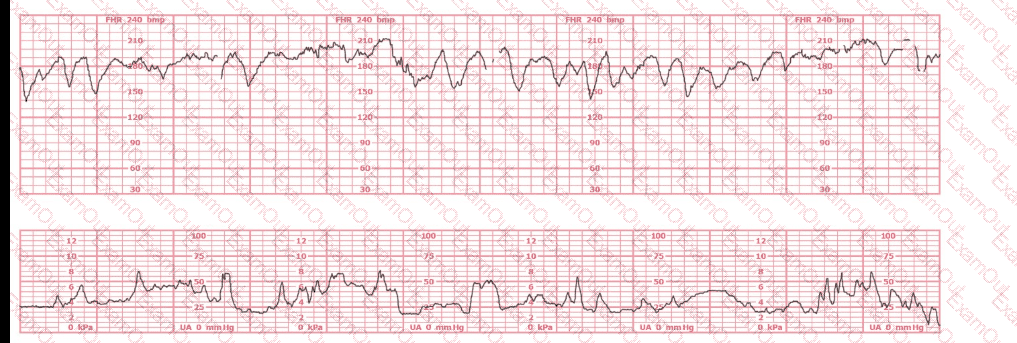

This tracing would be categorized as a